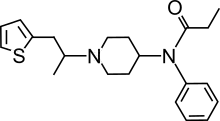

Anilidopiperidines